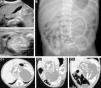

Se presenta un recién nacido a término, varón, con diagnóstico ecográfico de masa abdominal a las 25 semanas de gestación. Exploración física anodina. Valores séricos elevados de ferritina, LDH, β-HCG y FA; hemograma, función renal, α-fetoproteína y antígeno carcinoembrionario normales. Catecolaminas urinarias normales. La ecografía abdominal muestra una masa retroperitoneal sólida lobulada bien delimitada rodeada de líquido y con calcificaciones lineales en su interior que recuerdan a estructuras óseas (fig. 1A). En la radiografía de abdomen se visualizan estructuras óseas maduras simulando huesos largos en flanco izquierdo (fig. 1B). La TAC abdominal (fig. 1C) confirma los hallazgos y detalla la relación de la masa con importantes estructuras vasculares y viscerales. La exploración quirúrgica, realizada a los 5 días de vida, revela una masa encapsulada que se secciona obteniendo un líquido translúcido y una masa de aspecto fetiforme con las 4 extremidades y un vestigio de cordón umbilical de 8mm de longitud que continúa con un tejido membranáceo correspondiente a la bolsa amniótica (fig. 2). El estudio anatomopatológico describe una estructura fetiforme recubierta de piel con arrinia, anoftalmia, acráneo y raquisquisis. Se identifican lengua, gérmenes dentarios, tráquea, esófago, intestino, vejiga, tejido pancreático y testicular, glándula adrenal, columna espinal con médula ósea y pelvis. Se descartan signos de malignidad. A las 48h postexéresis presenta distensión abdominal, elevación sérica de parámetros inflamatorios y radiografía abdominal con neumatosis intestinal. Ante la sospecha de enterocolitis necrosante se inicia antibioterapia. En la reintervención quirúrgica se objetiva necrosis isquémica del íleon terminal hasta colon ascendente, secundaria a la ligadura de una rama de la arteria mesentérica superior. Se realiza hemicolectomía derecha, ileostomía distal y colostomía en colon transverso. El postoperatorio transcurre sin incidencias, con normalización de los valores de ferritina, LDH, β-HCG y FA. Se realiza reconstrucción intestinal mediante anastomosis término-terminal sin incidencias a los 3 meses. Su evolución a los 12 meses es excelente con adecuado desarrollo pondero-estatural.

A) Ecografía abdominal. B) Radiografía simple de abdomen, la figura ovalada remarca las estructuras óseas longitudinales. C) TAC abdominal: masa bien delimitada con estructuras calcificadas en su interior correspondientes a huesos largos y vértebras del FiF; C1) corte axial, C2) corte sagital; C3) corte oblicuo.